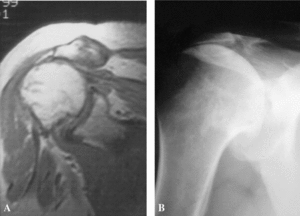

Tanto la cirugía abierta como la cirugía artroscópica son a menudo complementarias, pudiendo indicarse de forma correcta desbridamientos subacromiales artroscópicos, como cirugía paliativa en pacientes de mayor edad y con roturas masivas del manguito, así como realizar reparaciones tendinosas abiertas o asistidas con artroscopia en roturas pequeñas en pacientes en edad laboral y con requerimientos funcionales de mayor nivel. De hecho, los pacientes con mayor actividad laboral requieren una resolución de su síndrome doloroso y una recuperación completa de la función del hombro. En definitiva, en este grupo de pacientes, debe valorarse como tratamiento de elección la posibilidad de la cirugía abierta y reparadora del manguito rotador. Por el contrario, también en las roturas masivas del manguito, con afectación de más de un grupo muscular, con ascenso de la cabeza humeral, retracción mayor de 4 cm y degeneración grasa (fig. 4), la cirugía artroscópica, como gesto paliativo y descompresivo, por su baja morbilidad parece indicada en pacientes de edad avanzada, con dolor y con poca demanda funcional.

Figura 4. Estudios de imagen (RM y radiología simple) en rotura masiva de manguito rotador. Obliteración del espacio humeral.